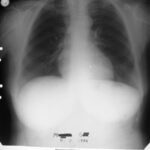

1995 - İlk Başvuru

Öksürük, ateş, sırt ağrısı - küçük hücreli anaplastik karsinom

Röntgende kitle küçülmüş durumda görüldü.

Röntgen tümörün tamamen kaybolduğunu gösterdi.

Radyolojik Kanıt: Röntgende tümör tamamen kayboldu